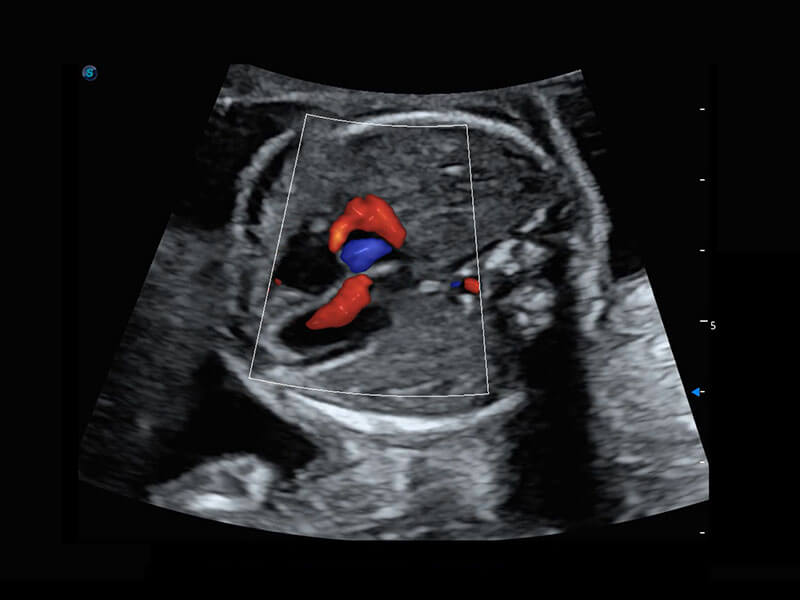

• 胎儿体循环

P60搭载一系列胎儿心脏成像技术,实现精细的胎儿心脏评估。